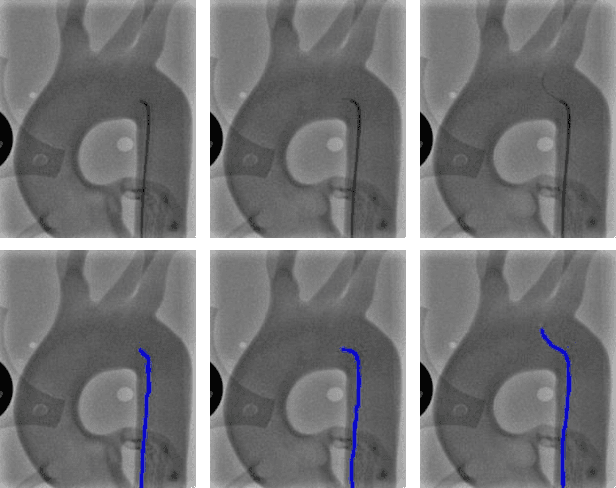

Abstract:Accurate real-time catheter segmentation is an important pre-requisite for robot-assisted endovascular intervention. Most of the existing learning-based methods for catheter segmentation and tracking are only trained on small-scale datasets or synthetic data due to the difficulties of ground-truth annotation. Furthermore, the temporal continuity in intraoperative imaging sequences is not fully utilised. In this paper, we present FW-Net, an end-to-end and real-time deep learning framework for endovascular intervention. The proposed FW-Net has three modules: a segmentation network with encoder-decoder architecture, a flow network to extract optical flow information, and a novel flow-guided warping function to learn the frame-to-frame temporal continuity. We show that by effectively learning temporal continuity, the network can successfully segment and track the catheters in real-time sequences using only raw ground-truth for training. Detailed validation results confirm that our FW-Net outperforms state-of-the-art techniques while achieving real-time performance.